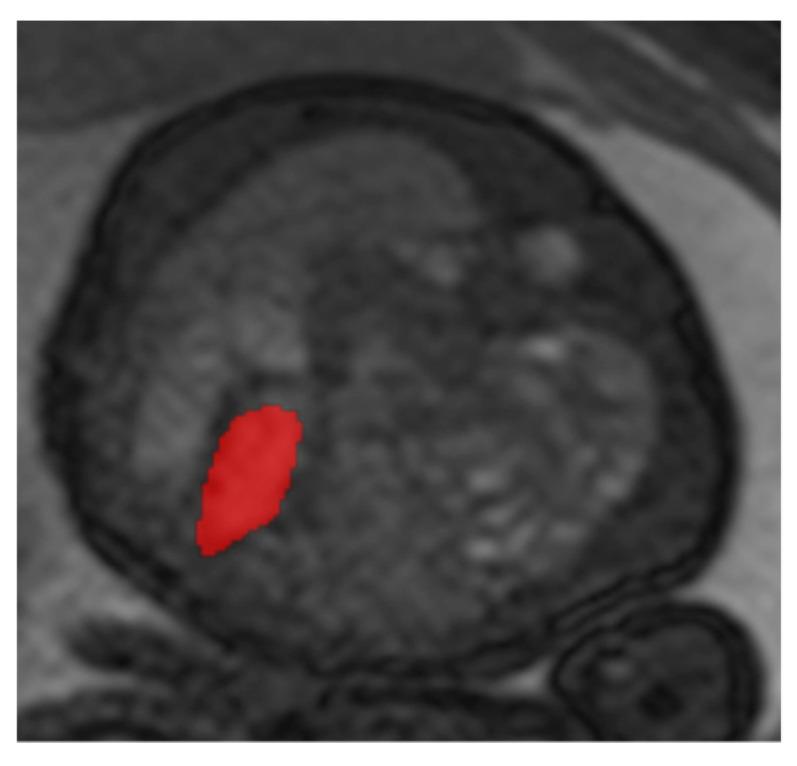

Fetal magnetic resonance imaging (MRI) is broadly used as a method for assessing prognosis in congenital diaphragmatic hernia (CDH). In addition to the extent of lung hypoplasia, determined by measuring the lung volume, cardiac impairment due to pulmonary hypertension and left cardiac hypoplasia is decisive for the prognosis. The percentage area of left ventricle (pALV) describes the percentage of the inner area of the left ventricle in relation to the total area, whereas the mediastinal shift angle (MSA) quantifies the extent of cardiac displacement. The prognostic value of pALV and MSA should be evaluated in terms of survival, the need for extracorporeal membrane oxygenation (ECMO) therapy, and the development of chronic lung disease (CLD).

胎儿磁共振成像(MRI)被广泛用作评估先天性膈疝(CDH)预后的一种方法。除了通过测量肺容积确定的肺发育不全程度外,因肺动脉高压和左心发育不全导致的心脏损害对预后也起决定性作用。左心室面积百分比(pALV)描述了左心室内面积相对于总面积的百分比,而纵隔移位角(MSA)则量化了心脏移位的程度。应从生存率、体外膜肺氧合(ECMO)治疗需求以及慢性肺病(CLD)的发生情况方面评估pALV和MSA的预后价值。